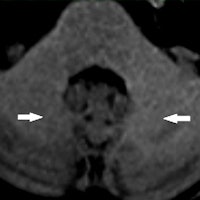

Image courtesy of Kanda et al, May 5, 2015, and Radiology.In 2015, evidence surfaced of lingering traces of gadolinium in the brains of patients who had received MRI contrast -- in some cases years after the scans occurred. Although it's still unclear whether the residual gadolinium is a safety risk, the news has prompted a review by the U.S. Food and Drug Administration (FDA) and the National Center for Toxicological Research (NCTR).